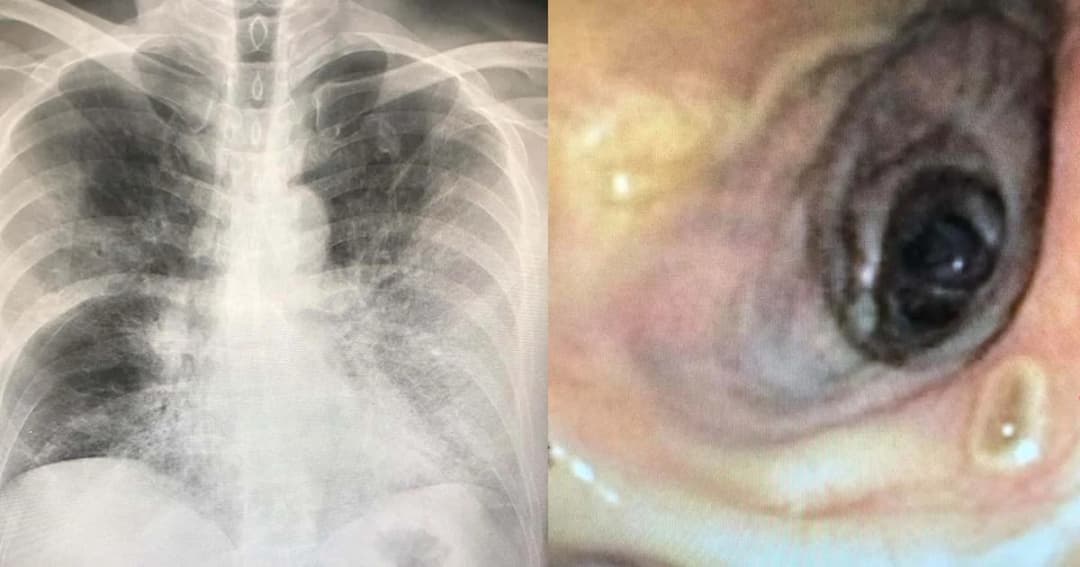

หมอเตือนป่วยไข้หวัดใหญ่ ติดเชื้อราในอากาศลุกลามจนเสียชีวิต